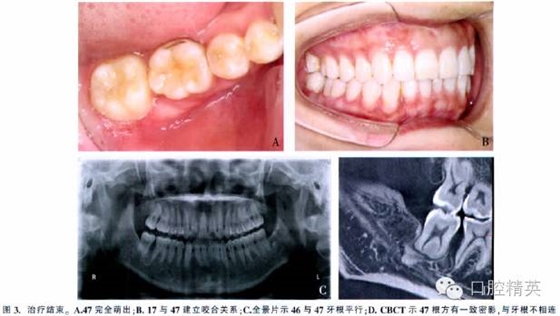

總療程為9.5個(gè)月。47牙周附著水平正常,與對(duì)牙合牙咬合關(guān)系良好。頭影測(cè)量顯示治療前、后下頜平面角和面下1/3高度無明顯變化。CBCT示右后牙牙根平行,47牙根長(zhǎng)度及根形未發(fā)生變化(圖3)。